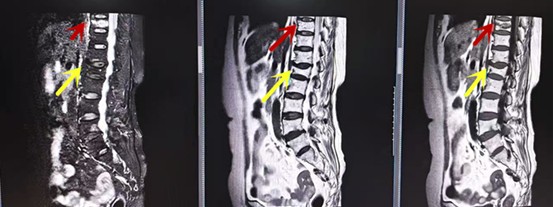

利器二:CT

CT利用X射線對(duì)人體檢查部位通過(guò)電腦切成若干層掃描,然后把每層的圖像都能顯示出來(lái)。CT相對(duì)于X光片具有更高的密度分辨力,可直接顯示X線片無(wú)法顯示的病變,觀察腰椎有無(wú)微小的骨折、骨質(zhì)有無(wú)破壞等骨質(zhì)情況、以及腰椎間盤突出、腰椎神經(jīng)根、椎管、椎間小關(guān)節(jié)的情況等。同時(shí)還可以通過(guò)后處理,重建腰椎矢狀位或冠狀位圖像,形成腰椎的3D圖像,更直觀地觀察病變部位,對(duì)腰椎手術(shù)風(fēng)險(xiǎn)具有提示作用,對(duì)手術(shù)方式的選擇具有指導(dǎo)意義,但是對(duì)神經(jīng)、脊髓損傷程度的顯示不如MRI,軟組織的分辨率仍有一定限制,對(duì)椎管內(nèi)病變顯示欠佳,且有一定的輻射。

箭頭提示椎間盤突出

從左向右依次為CT矢狀位重建圖像、三維重建圖像、軸位掃描圖像,箭頭提示腰1椎體爆裂性骨折